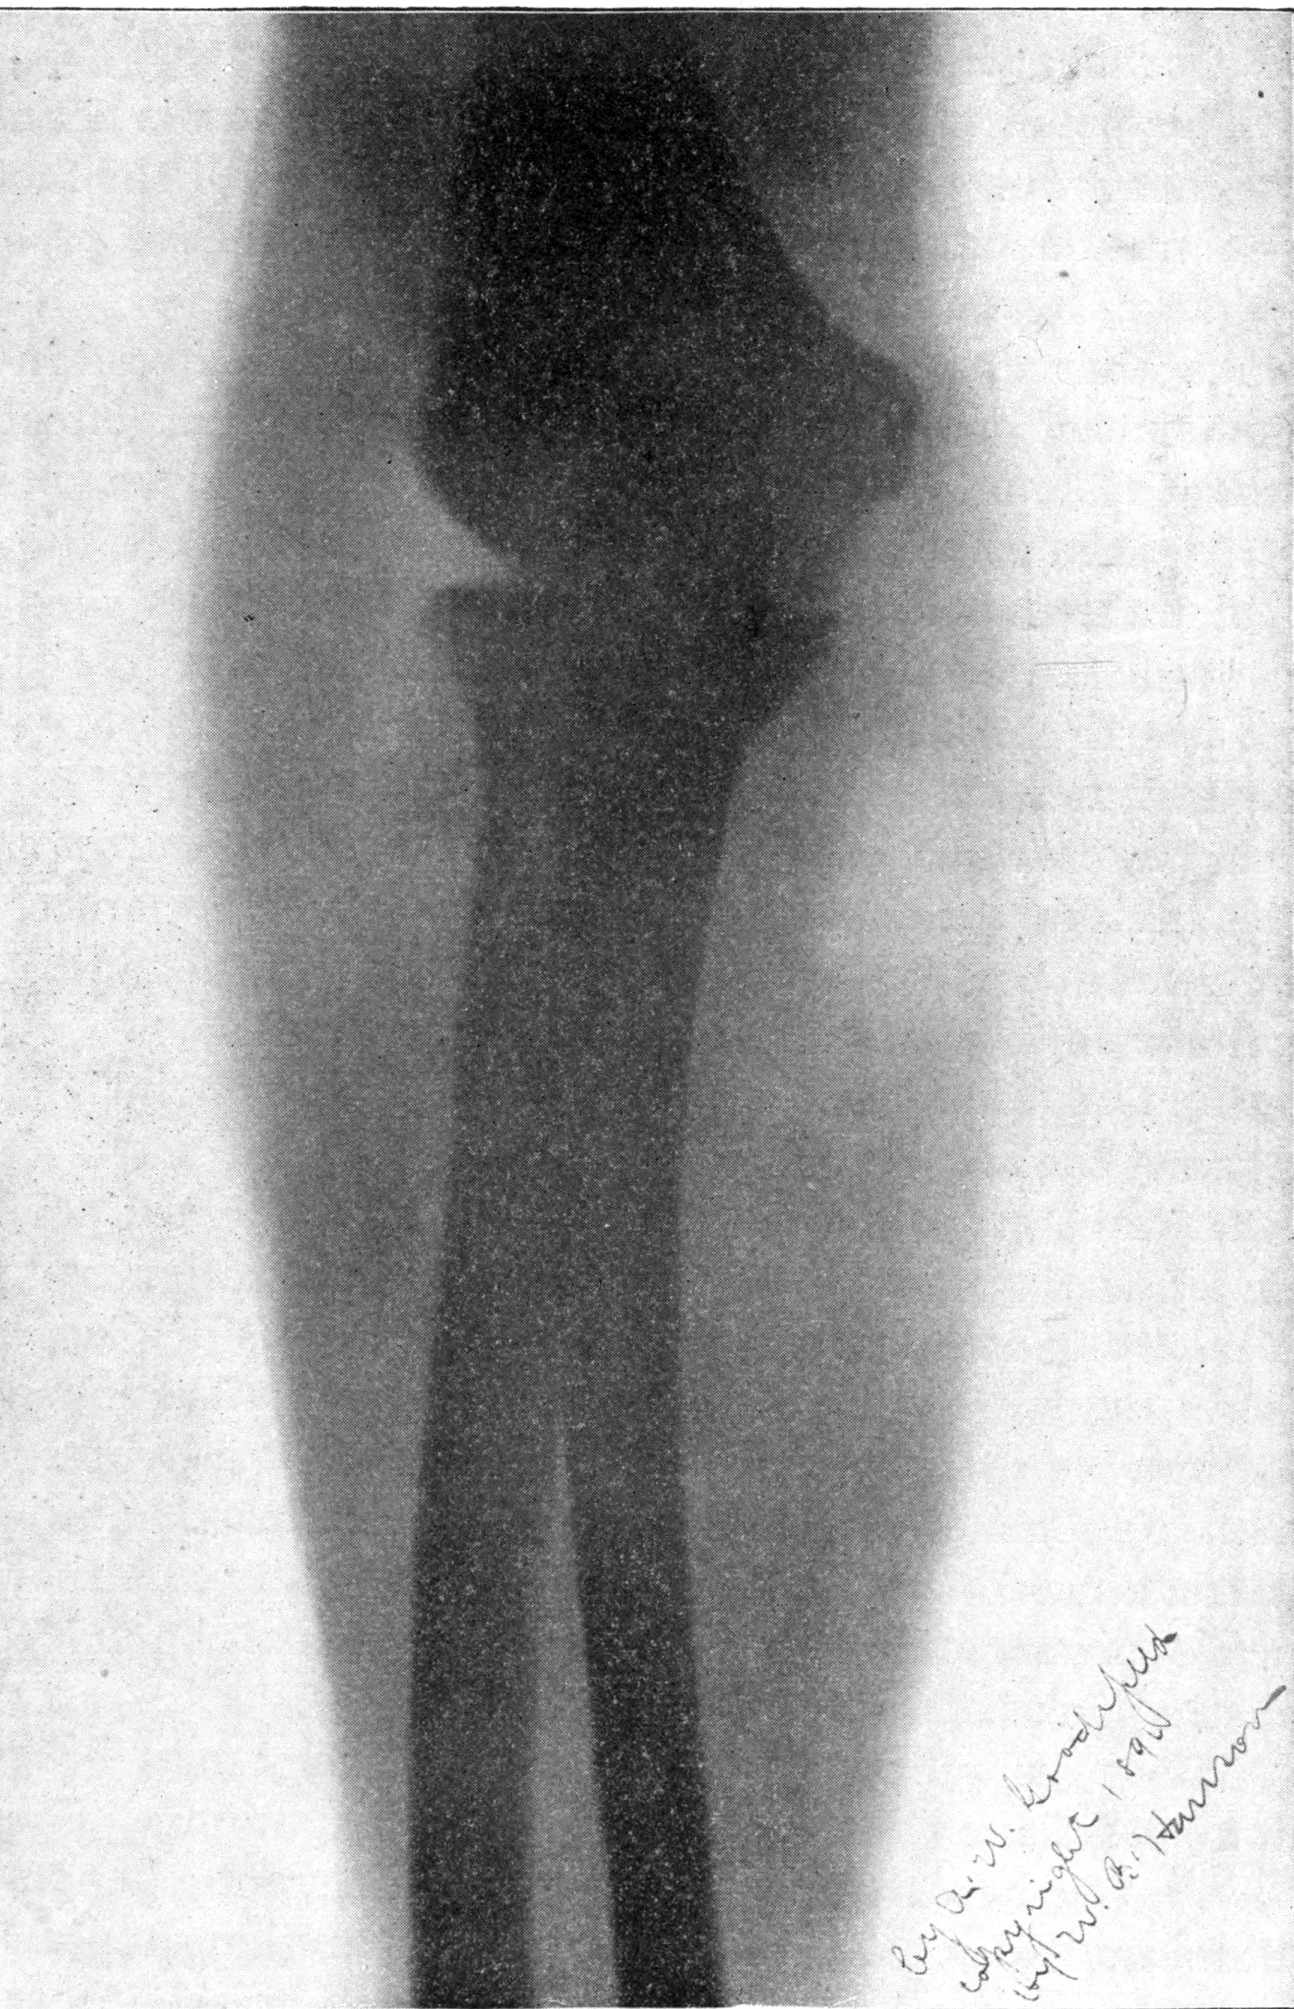

Fig. 4.—Knee, Knickerbocker Buttons, Bullet in Femur.